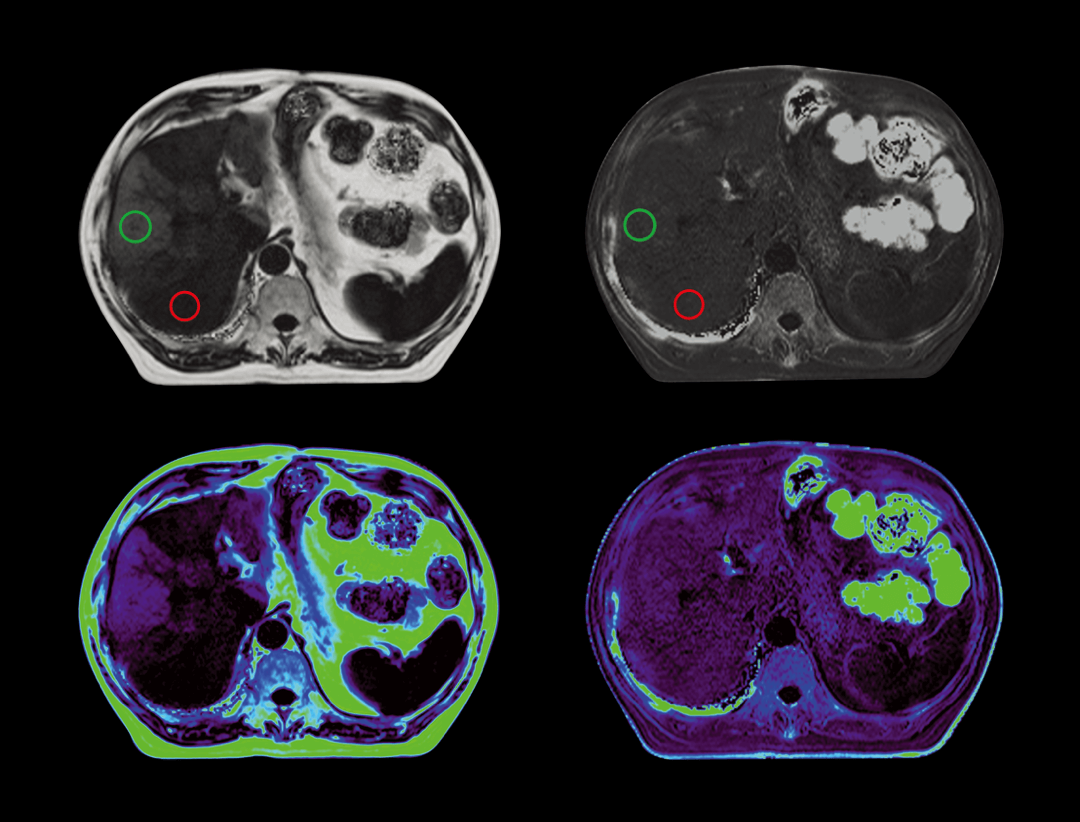

脂肪定量

无创检测组织内脂肪含量及铁沉积,一次扫描输出多参数图像,可以同时提供精确脂肪含量值以及铁沉积程度。